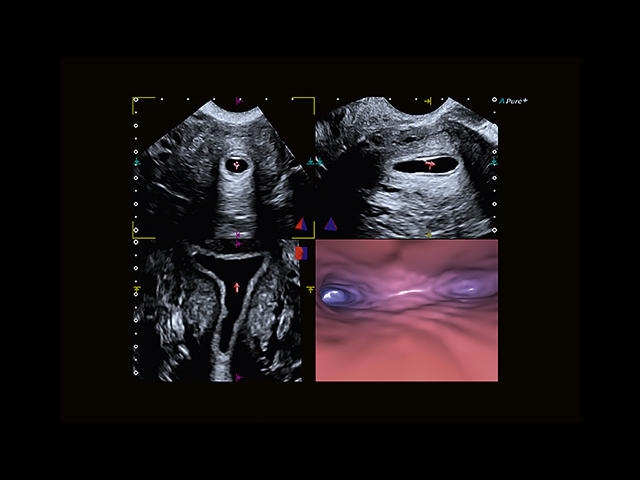

Обновленная версия легендарного УЗ-сканера. Стационарный аппарат экспертного класса Aplio 500 Toshiba NEW, визуализирует анатомические структуры в высоком разрешении. Модель позволяет выявить микрокальцификаты, новообразования, нарушения в работе сердца, сосудов и мышц. Присутствует функция виртуальной эндоскопии, 4D-сканирования, эластометрии тканей, УЗИ с контрастированием. За повышение качества изображения отвечают технологии ApliPure и Superb Microvascular Imaging. Первая задействует возможности пространственного и частотного кодирования, формирует цельный визуальный ряд с сохранением клинических маркеров. Вторая улучшает отображение микрососудистого русла, используя доплеровский эффект. Модель оснащена 21-дюймовым монитором, имеет 4 активных порта. Возможно подключение педиатрических, интраоперационных, лапароскопических и чреспищеводных датчиков.

• Fly Thru. Виртуальная эндосонография обеспечивает построение трехмерной модели полостей, протоков и сосудов в рельном времени, облегчает организацию инвазивных процедур и динамических исследований. Посредством Fly Thru можно установить шунты и стенты, проводить точные оперативные вмешательства.